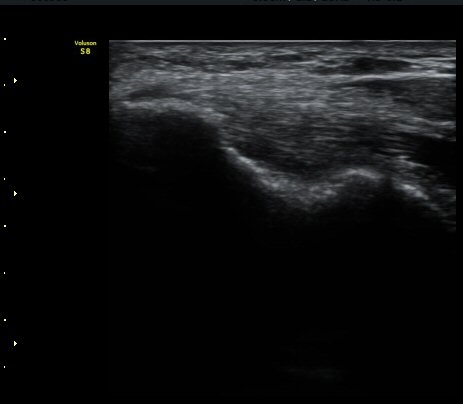

³»»ó°ú¿¡¼­ ¼Õ¸ñ±¼°î°Ç Á¾´Ü¸é°Ë»ç»ó ³»¤µ¾Æ°ú ÇÇÁú°ñÀÇ ºÒ±ÔÄ¢º¯È­¿Í ÈûÁÙ³» ¿¬°á¼º

¼Ò½Ç ¹× Àü¹ÝÀûÀÎ Àú¿¡ÄÚ ºÎÁ¾ÀÌ °üÂûµÈ´Ù(±×¸² 1, 2, 3). ±¼°î°Ç ÀϺδ Á¤»óÀûÀÎ °í¿¡ÄÚ

¼¶À¯ ¾ç»óÀ¸·Î °üÂûµÈ´Ù(±×¸² 4). ÈûÁ٠Ⱦ´Ü¸é °Ë»ç¿¡¼­µµ °Ç³» ¿¬°á¼º ¼Ò½Ç°ú Àú¿¡ÄÚ